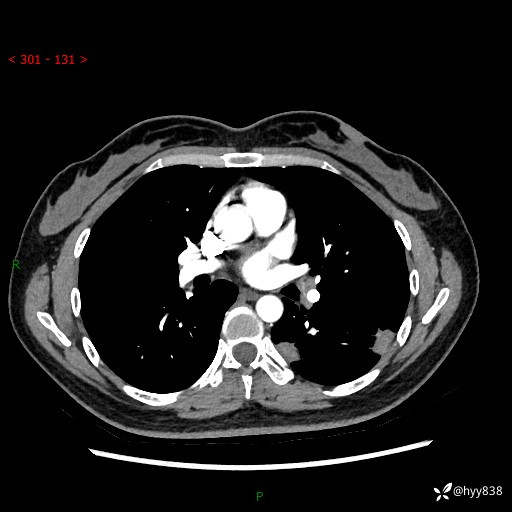

【患者信息】:36岁/女

【主诉】:左侧下胸部阵发性疼痛2周,乏力1周

【现病史及既往史】:患者自诉2周前饮酒后出现左侧下胸部阵发性疼痛,不随呼吸改变,无咳嗽咳痰、头晕头痛、咳血、呼吸困难等不适,于当地第一人民医院查胸部CT提示肺部感染,随后前往我院门诊给予抗感染(左氧氟沙星)治疗1周,自诉胸痛较前好转,感乏力、头晕,偶尔干咳,无咳痰,无发热、畏寒、胸闷、咯血、四肢酸痛、腹泻、腹痛等不适,门诊复查胸部CT提示:左肺下叶感染,病灶较前增加增大,遂以“肺部感染”收入我科。 起病以来,患者精神、饮食、睡眠可,大小便正常,体力体重无明显变化。

【检查】:胸部CT增强(外院平扫)